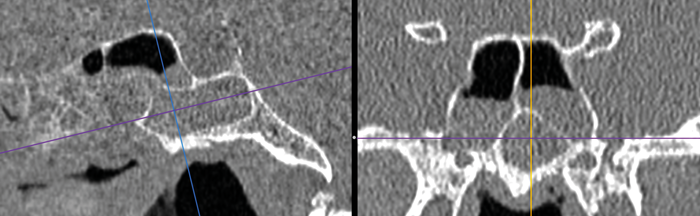

Preoperative sinonasal CT imaging is essential to FESS surgery. Ideally the CT data should be provided in thin-slices (less than 1mm thick) including the full volume of the paranasal sinuses. The images should be available during surgery in a 3 axis viewer, preferably one with the facility for multiplanar reconstruction (MPR).

Before the case, it is helpful to perform an MPR to align the axial slices with the palate and skull-base, while correcting any angulation of the coronal images to obtain symmetric views. Window-levels are optimised for bone definition, rotation corrected for each view, and the views maximised by zoom. We then study the scans from three different perspectives as follows.

Onodi cells - most easily seen on coronal views, especially after a well performed MPR.

An Onodi Cell.